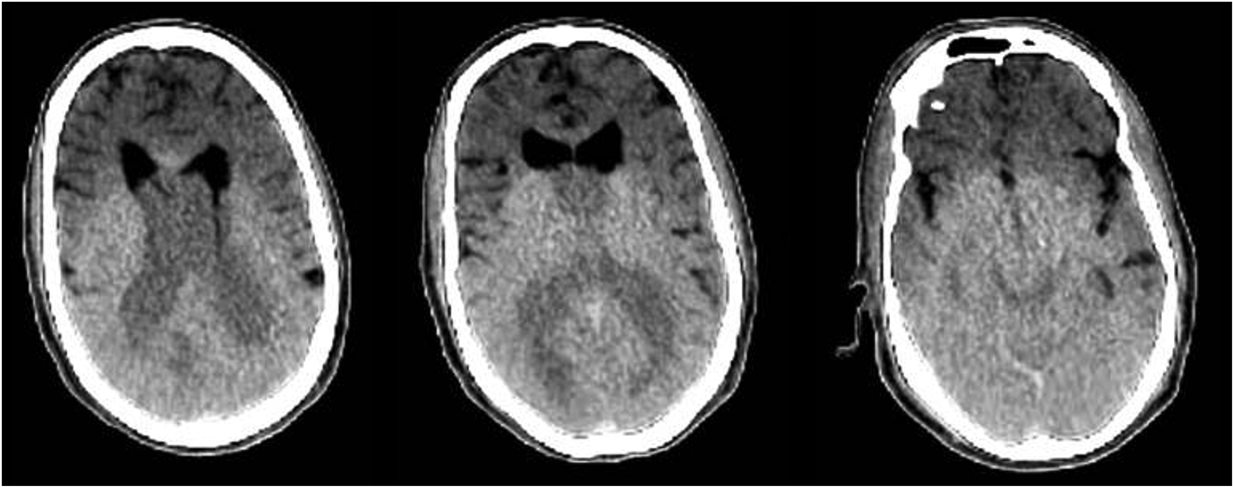

2. A 70-year-old male with a history of bilateral hand arthritis was discovered unresponsive outside his residence during a wellness check. Postmortem computed tomography (PMCT) images of the brain are provided (figure 2).

Assuming the brain findings in both cases represent the same radiology-pathology correlates, which of the following pieces of information would best explain the findings?